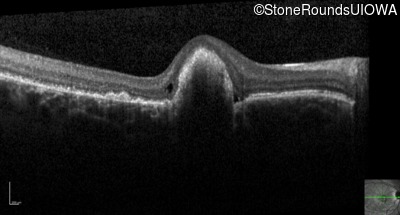

Optical Coherence Tomography - Right - 20/100 sc

Exemplar / OCT Stack

OCT Stack